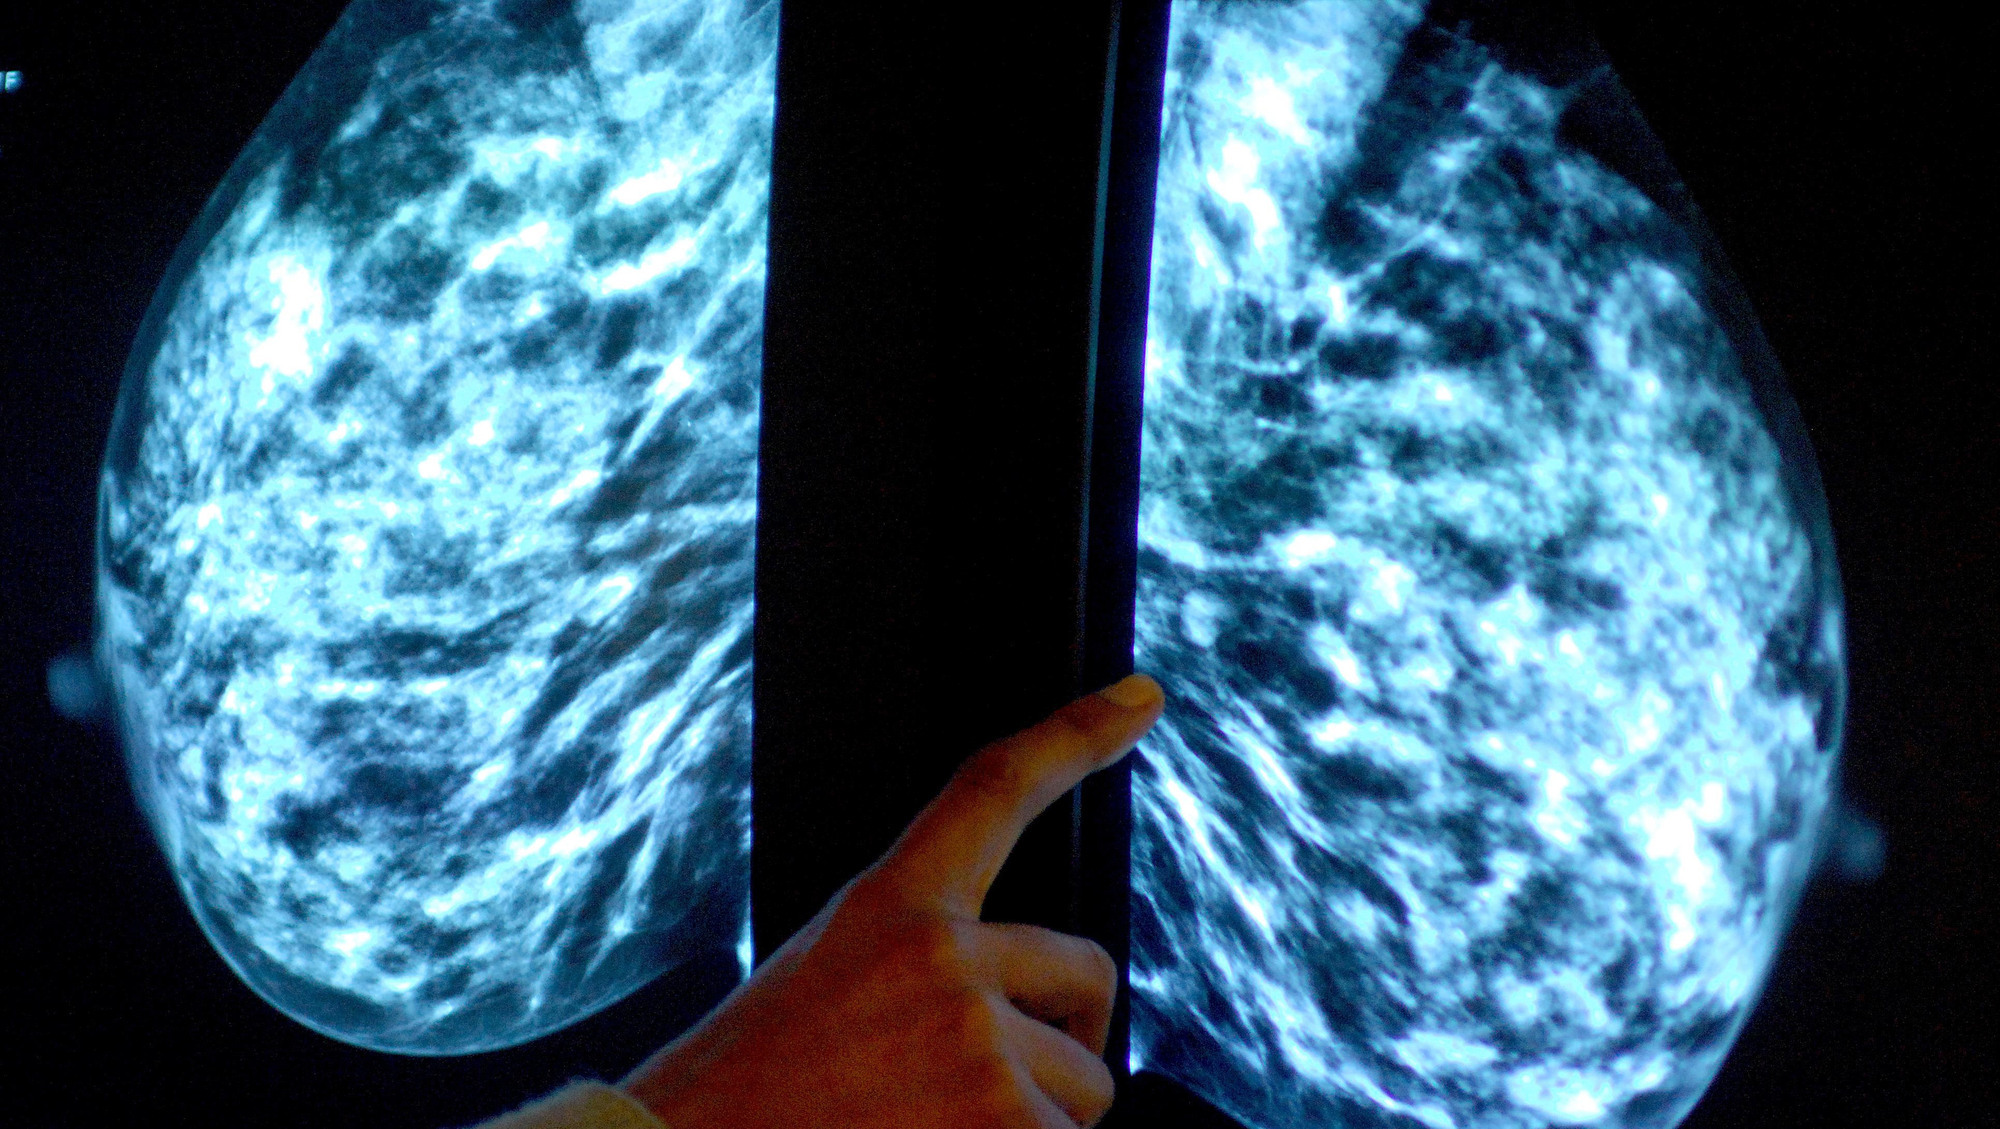

A new study has enabled scientists to study breast tissue in detail outside the body (Rui Vieira/PA)

Researchers say they have managed to keep breast cancer tissue viable for at least a week outside of the human body, paving the way for enhanced cancer treatments.

A new study found breast tissue could be preserved in a special gel solution, enabling scientists to examine it in great detail.